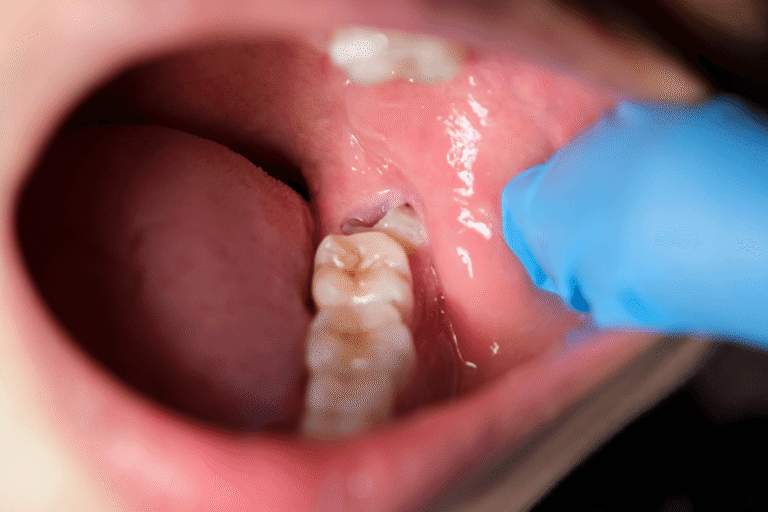

Напълно ретинираните мърдеци са изцяло скрити под венеца. Частично ретинираните мъдреци са видими, но само част от мъдреца е пробила над венеца. Неретинираните мъдреци са изцяло видими над зоната на венеца. Неретинираните мъдреци също могат да доведат до сериозни орални проблеми.

Кариес – Ретинираните мъдреци са изложени на по-висок риск от кариес в сравнение с останалите зъби. Мъдреците са най-задните зъби и поради това са най-трудни за почистване. Храната и бактериите много по-лесно се задържат между венеца и неправилно изникналите зъби.

Заболявания на венците – тъй като мъдреците са по-трудни за почистване, е много по-вероятно в тези зони да се стигне до заболявания на венците, които в дългосрочен план могат да доведат до много орални проблеми.